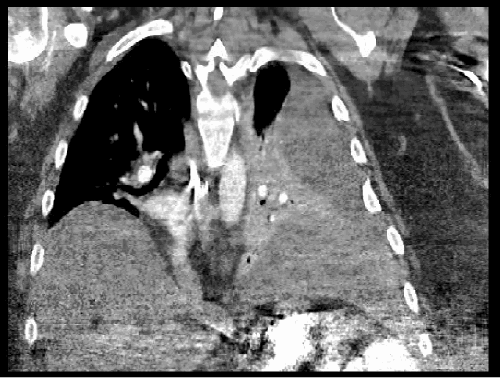

The patient was initially managed conservatively with bowel rest, intravenous hydration, and electrolyte repletion, targeting standard resuscitation parameters (mean arterial pressure >65 mmHg, heart rate <120 bpm, urine output ≥0.5 mL/kg/hr, capillary refill <2 seconds, and normalization of BUN, creatinine, electrolytes, and lactate). A nasogastric tube was placed for decompression, and intravenous analgesia was administered judiciously, avoiding narcotics where possible. Serial laboratory evaluations and physical examinations were performed to monitor for signs of worsening systemic inflammatory response, metabolic acidosis, increasing abdominal distension, or the development of peritonitis. Despite these measures, on hospital day five, the patient experienced a significant clinical deterioration, manifesting as sepsis and acute respiratory failure. A repeat CT scan at this time demonstrated a new, large, loculated, mixed-density pleural effusion on the left side (Figure 2). Crucially, this scan provided complete visualization of the hernia sac, revealing a persistent small bowel obstruction and a new extraperitoneal fluid collection within the abdominal wall, which appeared to be tracking superiorly into the pleural cavity (Figure 3).

Figure 2. CT Revealing Large Left Pleural Effusion. Published with Permission